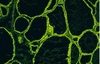

Figure illustrates 4 histological variations of Thyroid follicele appearance , define each one

Thyroid tissue

Thyroid tissue ;

Define the symbol and identify the stain used